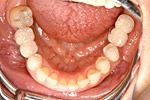

① 上と同一人物のかみ合わせから見た状態。

② 左下は普通では取りはずしの入れ歯しか入りませんが、インプラントにより、固定式の歯が入りました。